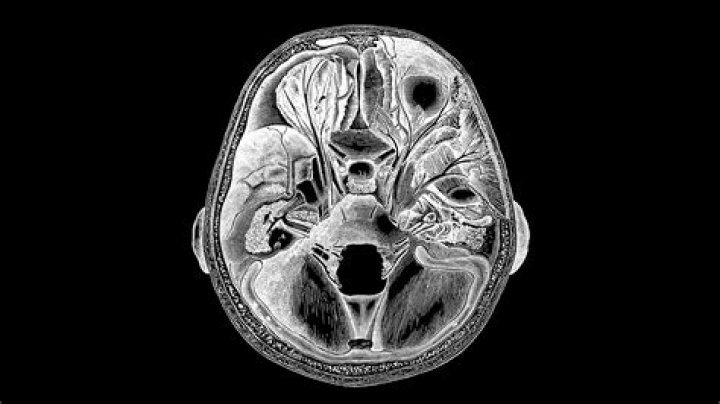

Why does Leucotomy lobotomy target white matter for destruction?

White matter comprises the axons, or nerve fibers, that connect the areas of gray matter and carry messages between them through electrical impulses. So a lobotomy was intended to sever the white matter between different areas of gray matter.

In lobotomy. …the procedure, replacing it with transorbital lobotomy, in which a picklike instrument was forced through the back of the eye sockets to pierce the thin bone that separates the eye sockets from the frontal lobes. The pick's point was then inserted into the frontal lobe and used to sever connections…

What does the frontal lobe do?

As those who watched the procedure described it, a patient would be rendered unconscious by electroshock. Freeman would then take a sharp ice pick-like instrument, insert it above the patient's eyeball through the orbit of the eye, into the frontal lobes of the brain, moving the instrument back and forth.